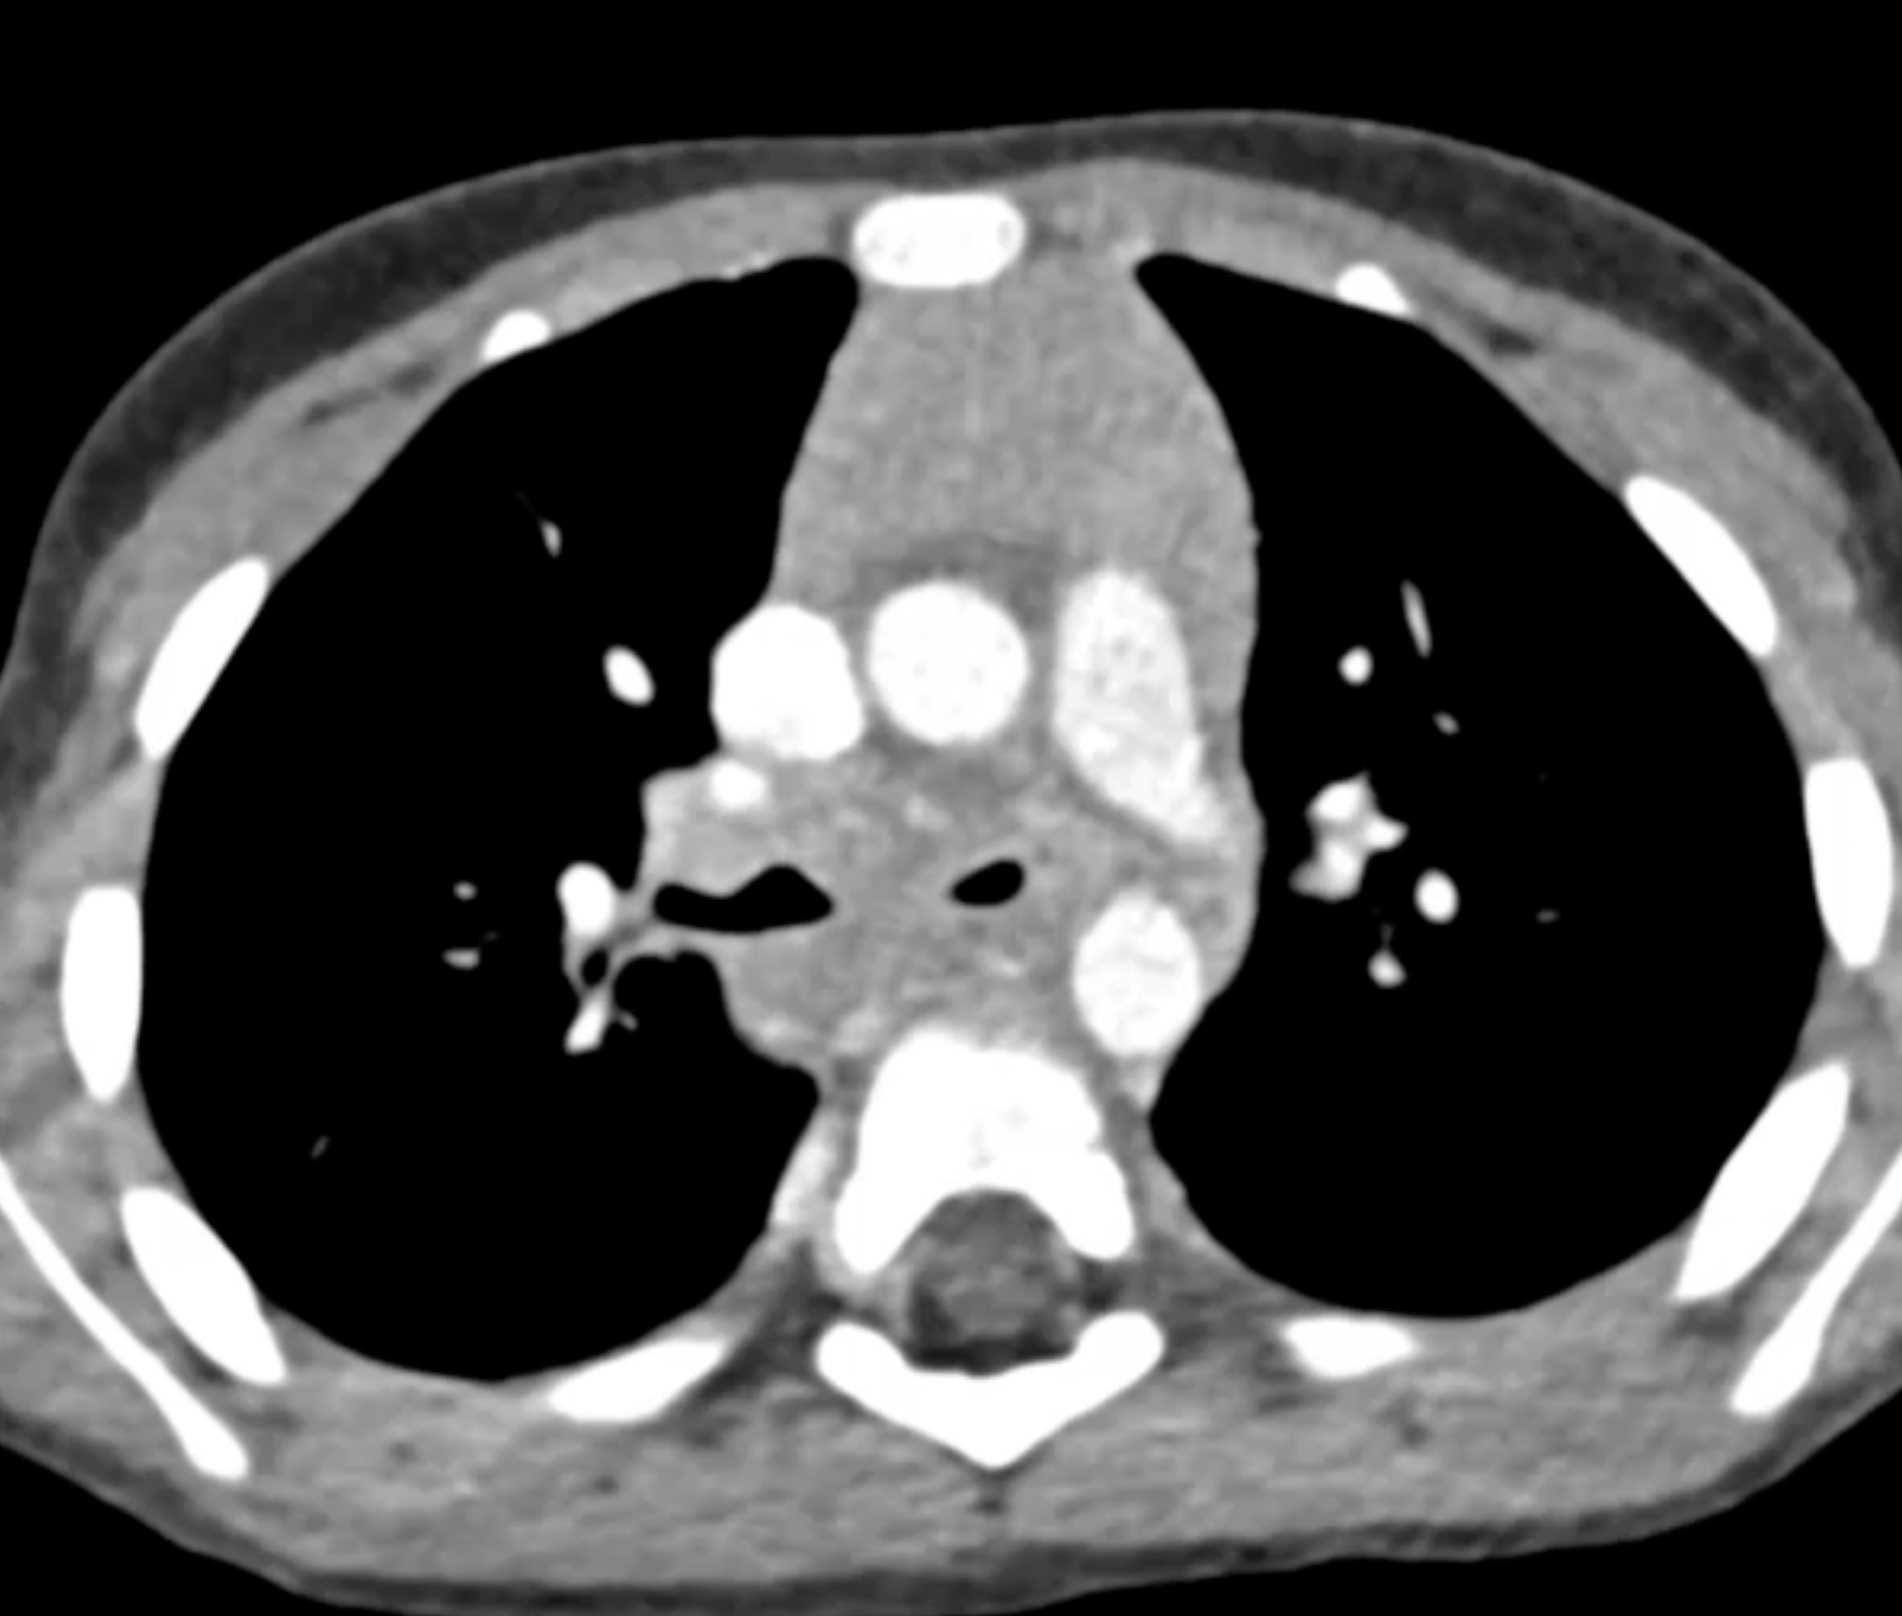

Histoplasmosis and Normal Thymus